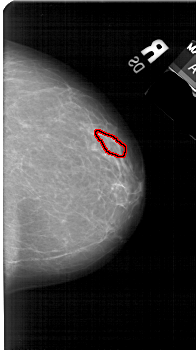

A_1548_1.RIGHT_CC

FILE: A_1548_1.RIGHT_CC.OVERLAY

TOTAL_ABNORMALITIES 1

ABNORMALITY 1

LESION_TYPE CALCIFICATION TYPE PUNCTATE DISTRIBUTION LINEAR

ASSESSMENT 3

SUBTLETY 1

PATHOLOGY BENIGN

TOTAL_OUTLINES 1

BOUNDARY